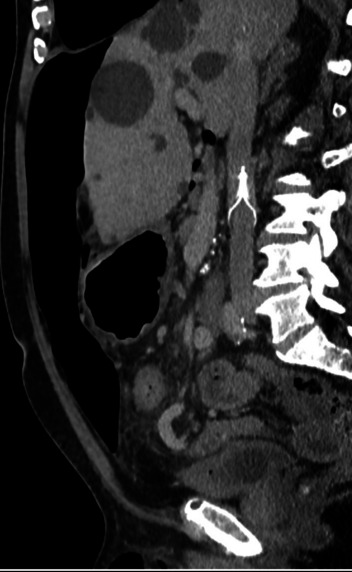

Results: Our seven-week perioperative protocol systematically integrates key preoperative interventions: bilateral abdominal wall botulinum toxin injections, respiratory prehabilitation, abdominal binder use, VTE prophylaxis with low molecular weight heparin (LMWH), planned IVC filter insertion, peritoneal dialysis catheter placement, and scheduled PPP insufflation sessions. Final surgical planning is guided by crosssectional imaging obtained one week preoperatively. Postoperatively, a structured IVC filter removal strategy, including cavogram assessment, is implemented to manage thromboembolic risk.